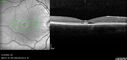

Pseudophakic cystoid macular edema (CME)158 views66 year old female 4 months following cataract surgery. Never had very good vision after surgery. On PF QID for one month. VA 20/50 in both eyes.